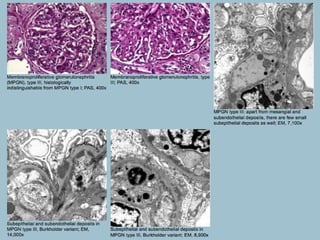

• Type I MPGN is the most common, “classic” type of primary MPGN,

with subendothelial and mesangial deposits and with strong C3 and

• Lobular appearance of glomeruli on low power magnification

• Mesangial expansion due to increased mononuclear inflammatory

cells and matrix

• Peripheral capillary loops are markedly thickened; on PAS and

silver stains, there are prominent double contour formations (“tram

tracking”)

• Immunofluorescence:

• There is fine granular deposition of IgG and C3 in the

mesangium and along the peripheral capillary loops; the reactivity

for C3 is usually very strong, commonly stronger than reactivity for

IgG

• Electron microscopy:

• Visceral epithelial cells: Focal, sometimes marked effacement of

visceral epithelial cell foot processes

• Glomerular basement membranes: Prominent subendothelial

widening due to cellular interposition and electron-dense deposits;

secondary basement membrane forms under the displaced

endothelium (double contour formation)

• Glomerular endothelial cells: Show loss of fenestrations and other

non-specific changes; they do not contain tubuloreticular structures

• Mesangium: Mesangial expansion due to increased number of

mononuclear inflammatory cells, an increase in the amount of

matrix and a presence of electron-dense deposits

(MPGN), type III (Burkholder, and

Strife and Anders variants)

• Type III membranoproliferative

glomerulonephritis (MPGN) consists of two

variants; Burkholder variant (MPGN type I

with subepithelial deposits) and Strife and

Anders variant (complex intramembranous

and subendothelial deposits, with marked

basement membrane irregularities). Electron

microscopy is essential in distinguishing these

variants from classic type I MPGN.

• Glomerular basement membranes: In the Burkholder variant, in

addition to subendothelial deposits similar to MPGN type I, there

are subepithelial, sometimes “hump”-like electron-dense deposits.

In the Strife and Anders variant, there are complex

intramembranous and subendothelial deposits, with marked

basement membrane irregularities; there is breakage, lamellation,

and disrupted appearance of the basement membranes

matrix, and a presence of electron-dense deposits